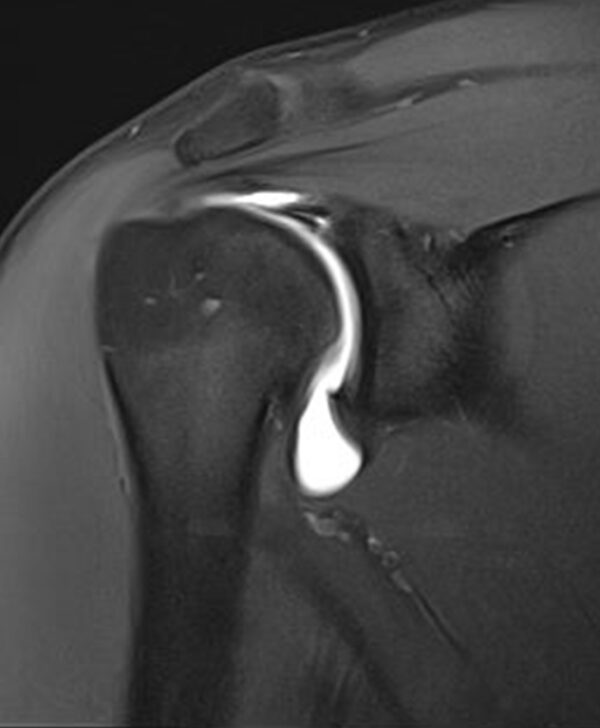

MR arthrogram testing :

State-of-the-art diagnostic test. An MR arthrogram can often produce a higher level of accuracy than a standard MRI for evaluating joints, bones, bones, and muscle conditions. As a two-part test, an MR arthrogram requires an injection of contrast dye into the joint, not the vein, as in a standard MRI. The injection is guided by X-ray technology for accuracy and is typically painless. The injection is followed by a 3T MRI to achieve high-definition, accurate images of the joint structure.

Candidates for MRI Arthrograms

- This testing procedure can be far more sensitive than a standard MRI for certain injuries. Your physician may order this advanced test if you have suffered an injury, are experiencing persistent or unexplained pain or discomfort, if the range of motion is affected, or the joint is not functioning correctly.

- The test may also be ordered by your physician to identify other problems such as tears in the ligaments, tendons, cartilage, or joint capsule or to diagnose damage from a series of joint dislocations, or evaluate the condition of a prosthetic joint.